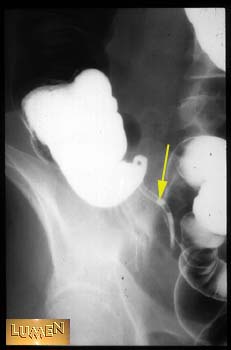

Question: Identify.

Answer

Appendix.